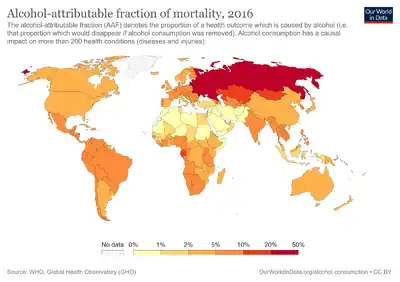

Epidemiology of alcohol-related cancers

Global Prevalence of Cancer Diagnoses Attributed to Alcohol Consumption

In 2020, approximately 740,000 cases of alcohol-related cancers were identified globally[6][7] with

- 58% of cases (430,000) residing in Asia

- 25% of cases (180,000) residing in Europe

- 8% of cases (60,000) residing in North America

- 5% of cases (39,000) residing in Latin America and the Caribbean

- 3% of cases (23,000) residing in Africa

- 1% of cases (7,000) residing in regions termed "other."

More than three-quarters of the 740,000 cases were in men.[8]